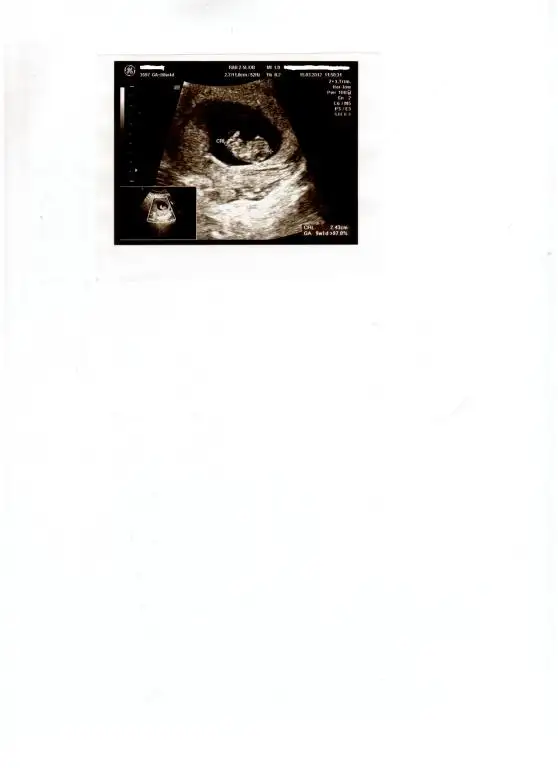

ekledim sanırım benim şu anda normalde 10. haftam bitti ama ultrasona göre 5 gün gerideyiz zaten bizim döllenme cok geç olduğu için normal dedi doktor.

kalbi pıt pıt pıt atıyodu onu görüp işe gelmek çok zevklidi şimdi 2 hafta beklicem yine nasıl beklicem bilmem